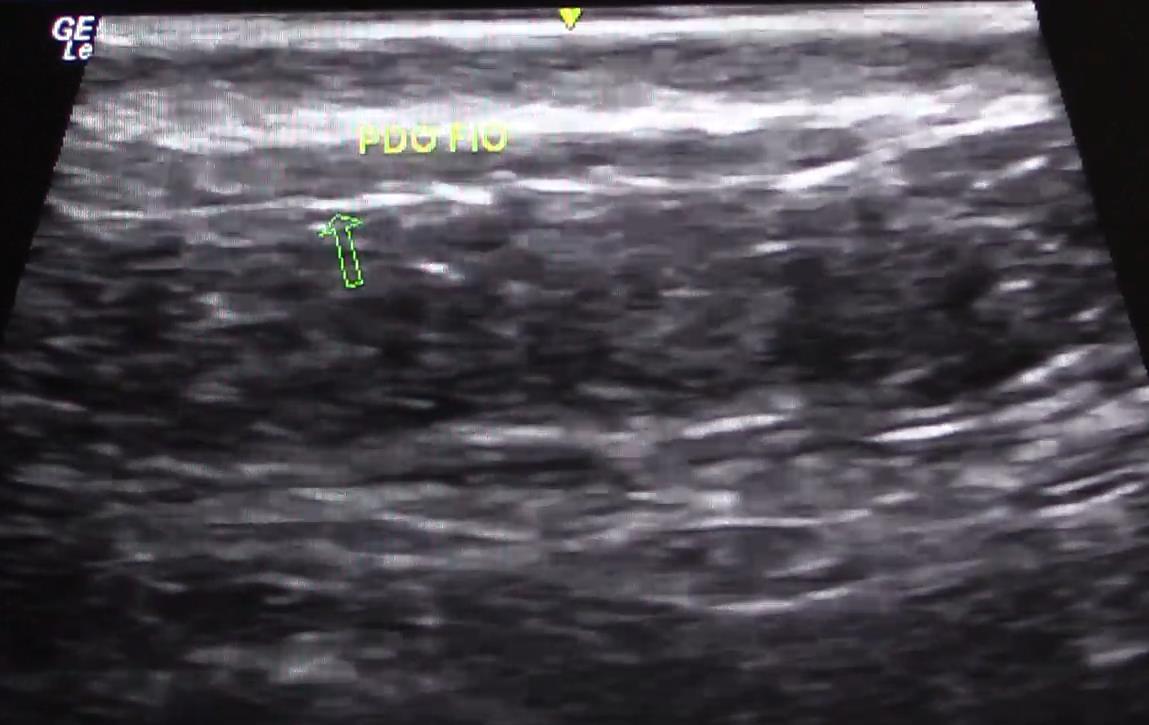

1.2 – PLANO DE APLICACIÓN

Fuente: Ecografía realizada por la Dra. Cristiane Ribeiro

18